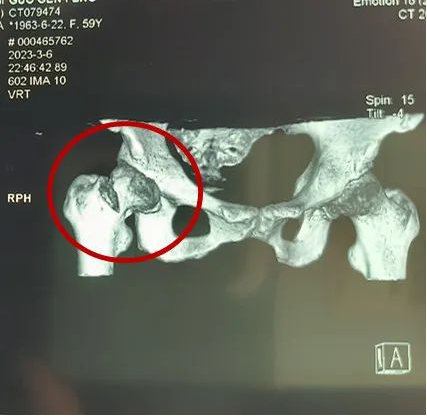

一次意外摔倒,59岁的郭女士右髋部剧烈疼痛,活动受限,行X线检查示:右股骨颈骨折(Garden Ⅲ型),收住我院创伤骨科。

患者术前影像